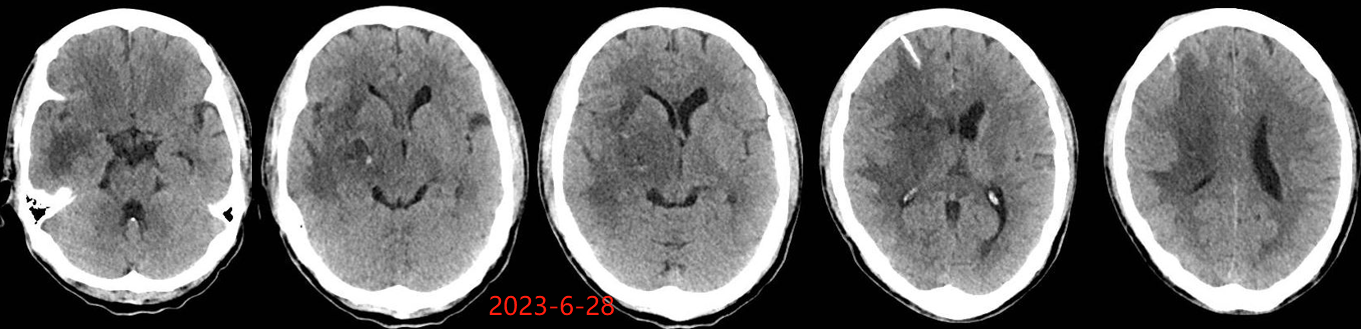

入院后于当地医院完善头颈部CTA检查未见明显血管发育异常,于2023-6-7行血肿钻孔引流术+脑室内颅内压监护探极置入术,引流一周后拔除引流管,期间未行尿激酶注射,患者反应情况逐渐好转,肌力未见明显改善。于出血后3周左右脑水肿基本消退后出院行康复治疗,治疗过程中患者肌力曾有所改善,左侧肢体肌力最好可达3级。术后3月左右患者一般状态逐渐变差,无发热,神志逐渐进展为昏睡状态,左侧肢体肌力1级,复查颅脑CT示水肿较前明显加重,颅脑MRI示右侧基底节区长T1长T2团块状病变,内有囊变,呈不均匀菜花样强化,考虑为高级别胶质瘤可能性大。遂行开颅病灶大部切除+去骨瓣减压术,术后病理提示高级别胶质瘤伴囊变,后续行同步放化疗STUPP方案,PTV:60Gy/30F/6周,替莫唑胺350mg化疗。患者右侧基底节区病灶相对稳定,2024-9-3复查颅脑MRI可见脑室内新发病灶。患者目前KPS 60分,神志清醒,精神差,反应迟钝,语言对答部分切题,右侧肢体自主活动,左侧肢体肌力2级。

胶质瘤出血灶周围水肿一般较广泛,同血肿期龄存在明显不符的征象,出血后早期即有明显水肿,此时并非血肿引起,而是肿瘤机械压迫、脑皮质受损,肿瘤细胞的分泌作用及细胞毒性等多因素共同作用所致,且水肿持续时间长。 高血压性脑出血的水肿一般在出血后 3 h 出现,48 h 达高峰,4 d 后开始逐渐消退,2-3 周后基本消失。该患者脑水肿出现的时间相对较早、重,且持续时间长,有别于一般的高血压脑出血。若该患者若第一次出血行钻孔引流时,术中能留取标本查到肿瘤脱落细胞,则会使该患者的诊断提前;当然对于该患者也不能完全排除单纯脑出血后,周围脑组织水肿缺氧等微环境的改变诱发胶质瘤的发生。总之,对于既往无脑出血高危因素且脑血管检查未见明显异常的脑出血患者,若脑水肿出现早且持续时间长,应警惕肿瘤卒中可能。